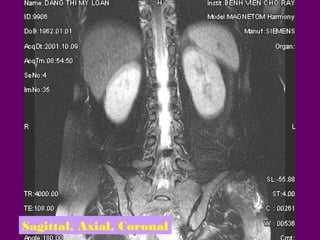

-Sagittal, Axial, Coronal

Sagittal, Axial, Coronal